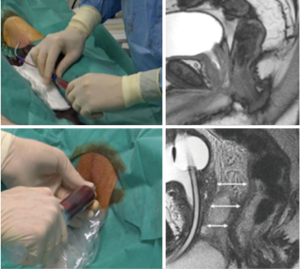

Thermoprotection of the urethra, used during cryosurgery, is achieved both by an irrigation of warm saline serum through a vesico-urethral catheter and by the monitoring of the sphincter’s temperatures (Figure 4). The thermocouple is inserted through the grid under MRI-guidance in the sphincter and thermometry is monitored to stop the procedure when the urethral temperature is below 15 °C.

In addition, thermoprotection of the urethra during cryosurgery is achieved by irrigation of the bladder with warm saline using a catheter placed in the bladder and by monitoring the urethral sphincter’s temperature (Figure 4). A thermocouple probe is inserted through the grid under MRI-guidance into the urethral sphincter. Urethral temperature is then monitored by a thermometry which discontinues the procedure when the urethral temperature is below 15 °C.